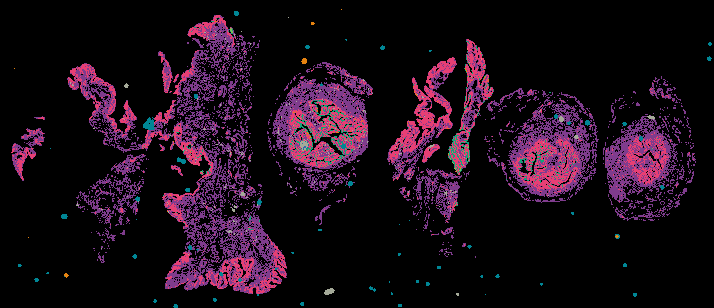

Micronuclei Rupture in High-Grade Serous Ovarian Carcinoma (HGSOC)

From 'Multimodal Spatial Profiling Reveals Immune Suppression and Microenvironment Remodeling in Fallopian Tube Precursors to High-Grade Serous Ovarian Carcinoma'.